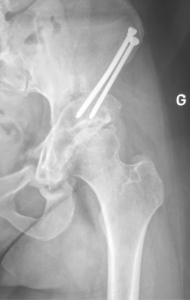

L’intervention se fait sous anesthésie générale. la cicatrice fait quelques centimètres, de par l’approche mini invasive. Quatre coupes osseuses sont effectuées, sous contrôle radioscopique, préservant la colonne postérieure de l’os iliaque. Ces coupes permettent de détacher le cotyle de l’os iliaque, puis de le réorienter correctement. Le positionnement du cotyle est vérifié par des radiographies sous amplificateur de brillance. L’ostéotomie péri-acétabulaire est généralement fixée avec deux vis.